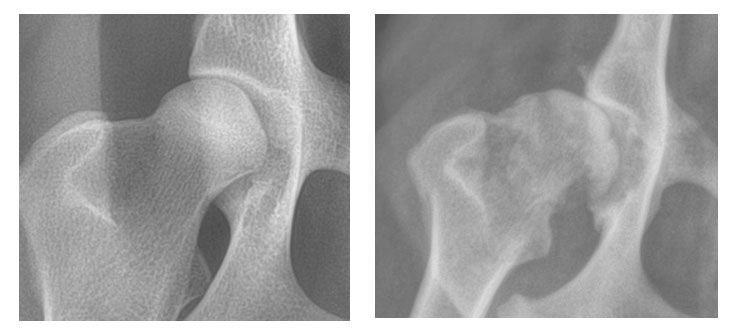

Vergleich

Hier in der Vergrösserung der Vergleich einer gesunden und einer Hüfte mit HD. Der Hüftkopf ist luxiert und durch die überhöhte Beweglichkeit hat sich starke Arthrose gebildet.